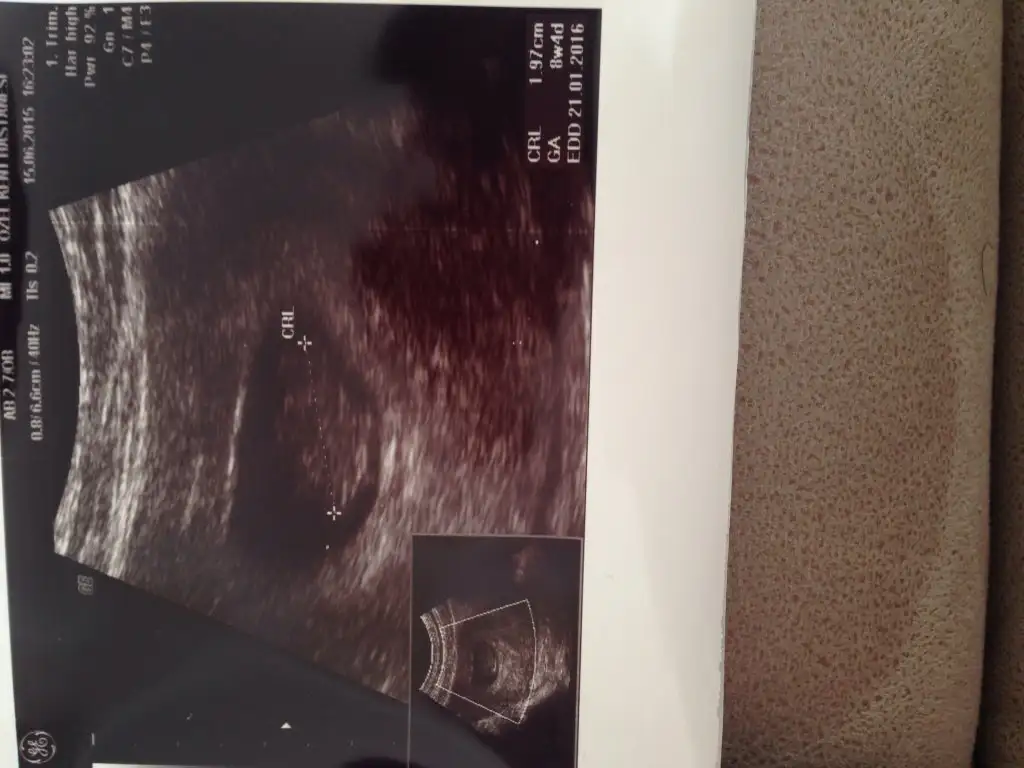

kızlar bebişimin kalp atışını sesini duymasam da 6+1 ken görmüştük bugün de 8+4 olduk ve duyduk çok şükür :KK200::nazar: Rabbim herkese nasip etsin inşallah sağlıkla kucağımıza alalım :anneadayı: Bu da yeni resmimiz